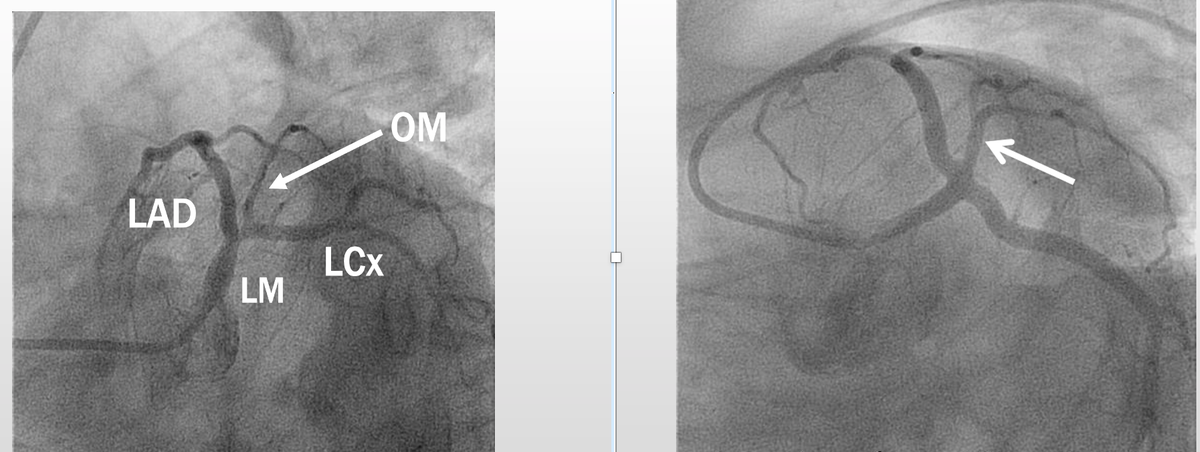

Basics of Cath angiography